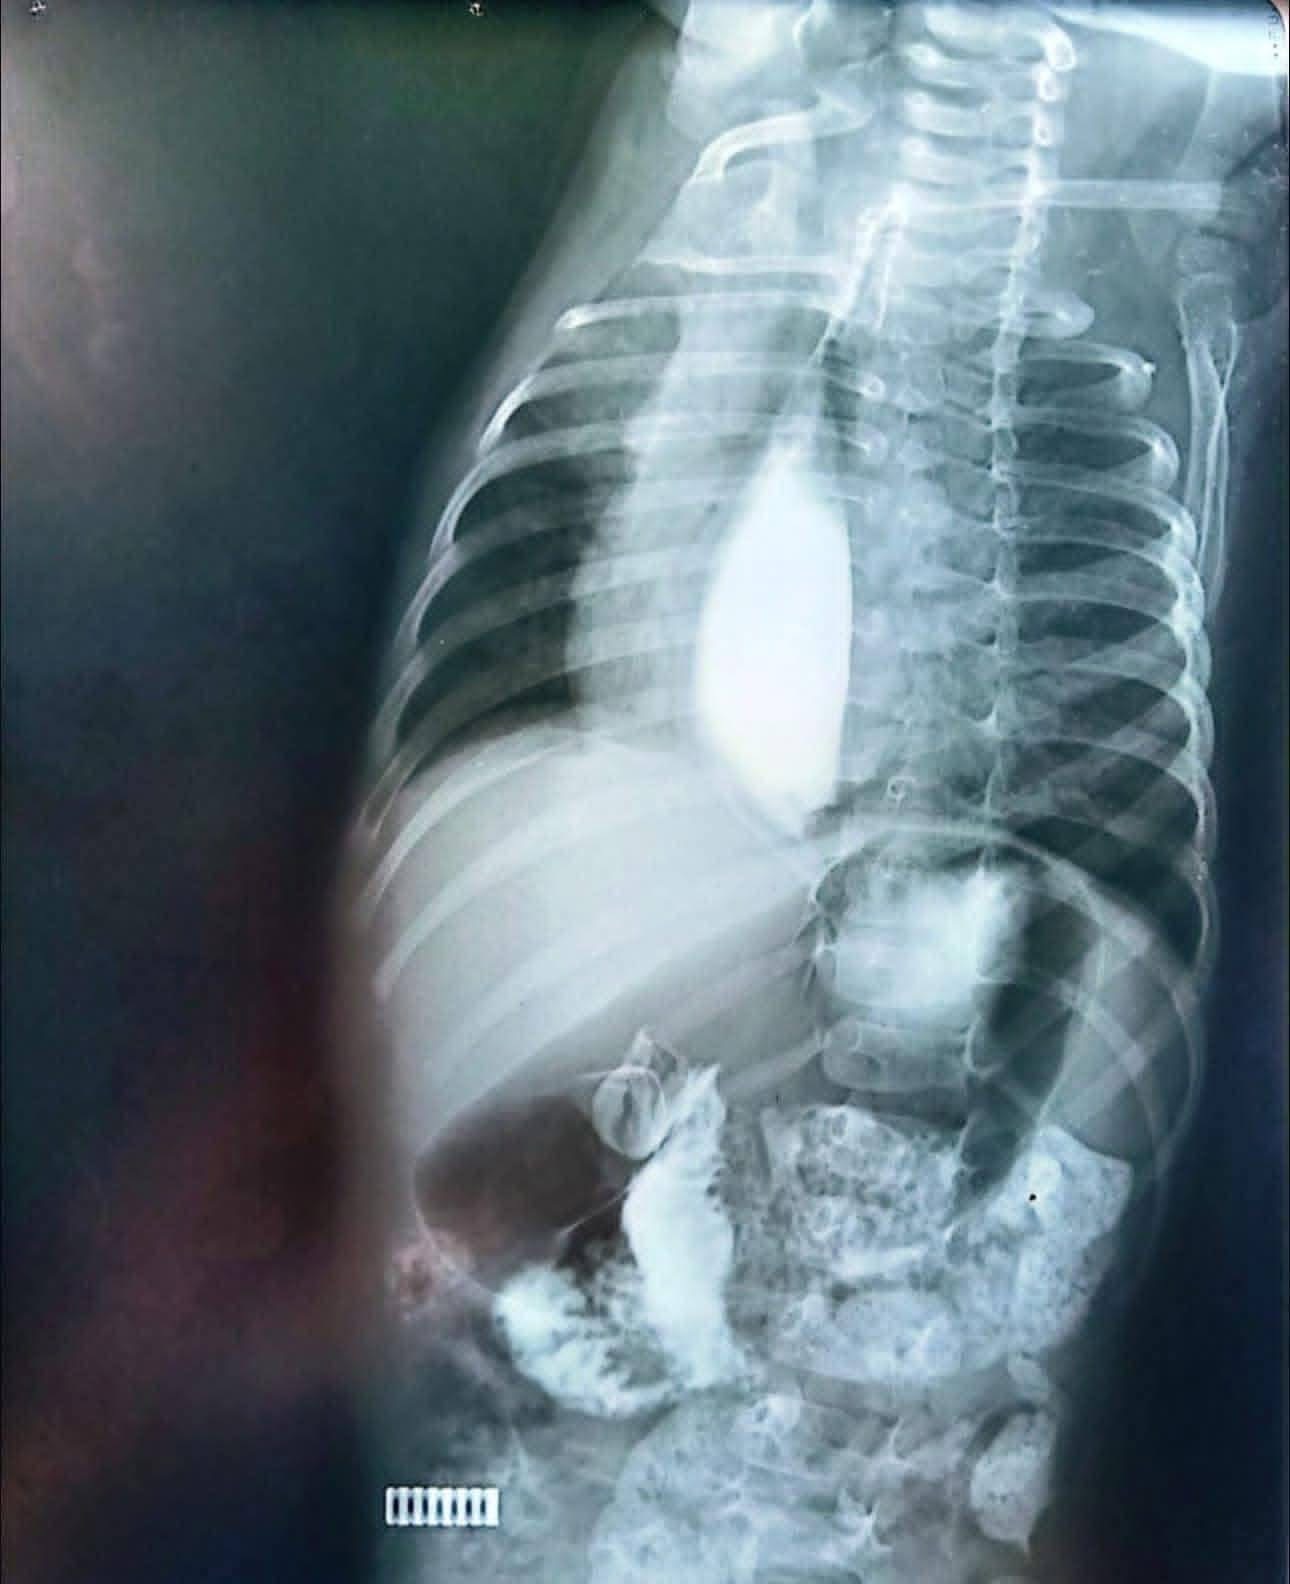

أشعة مقطعية